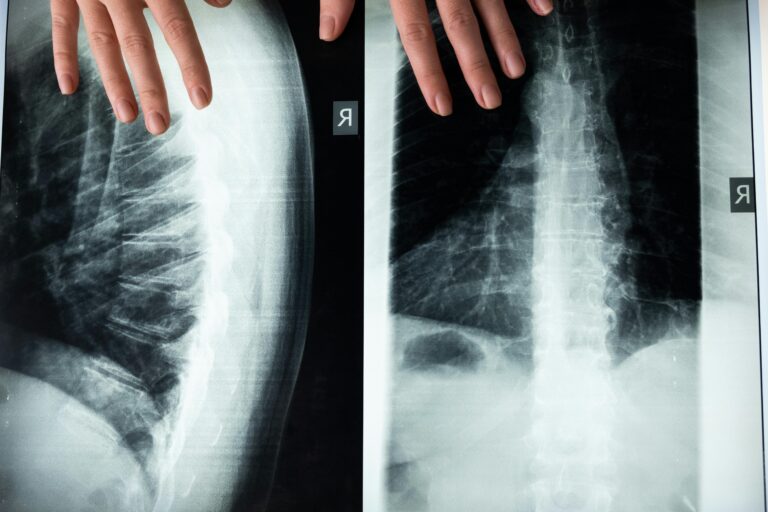

Cervical Disc Conditions

Cervical disc problems may develop from aging, injury, or repetitive strain. Symptoms can include stiffness, radiating arm pain, numbness, or reduced range of motion.

Nerve-Related Neck Conditions

Nerve compression in the cervical spine can cause radiating pain, numbness, or weakness extending into the shoulders and arms.